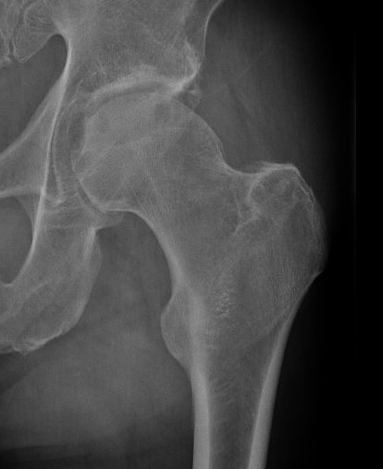

Etiology

Primary OA: 50%

Secondary OA: 50%

Secondary OA

SUFE Perthes

DDH Protrusio

Trauma

Paget's AVN

Sepsis

FAI